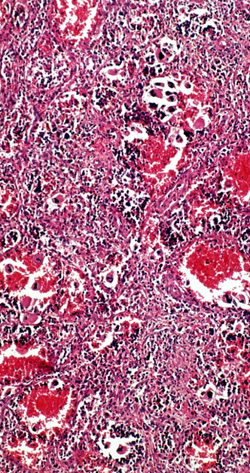

Mutasjonen i genet for tyrosinkinasen JAK2 i kromosom 9p24 er til stede hos over 95 % av pasienter med polycytemia vera og hos 50 – 60 % av pasienter med essensiell trombocytose eller primær myelofibrose. De sistnevnte pasientene har dårligst prognose. I tillegg til allmennsymptomene nattesvette, hudkløe og beinsmerter har mange også magesmerter og tidlig metthet som følge av forstørret milt.

I to fase 3-studier har man undersøkt effekten av Jak2-hemmeren ruxolitinib mot placebo (1) og beste alternative behandling (2) på reduksjon av milt og sykdomsrelaterte symptomer. Det gjaldt både ved primær myelofibrose og der sykdommen opptrer sekundært til polycytemia vera og essensiell trombocytose. Pasienter som ble inkludert hadde høy risikoskår og forventet levetid < 5 år.

Ruxolitinib ga reduksjon av miltstørrelsen sammenliknet med placebo (35 % reduksjon) (1) henholdsvis beste alternative behandling (42 %) (2). Samtidig viste begge studier en klar bedring av sykdomsrelaterte symptomer og rapportert livskvalitet. Den placebokontrollerte studien viste også livsforlengelse ved behandling med ruxolitinib (1). Anemi og trombocytopeni var de mest vanlige bivirkningene.